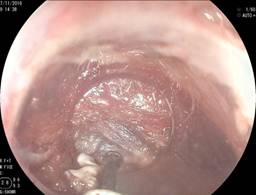

Durante los nueve años que duró el estudio, hemos tenido algunas modificaciones de la técnica y accesorios utilizados para la miotomía del músculo cricofaríngeo. De forma inicial se realiza endoscopia convencional, se procede a aspirar el material alimenticio que se encuentra en el divertículo y que limita la visión.

En los primeros 10 pacientes una vez identificada la luz del esófago, se introdujo una guía metálica a la cavidad gástrica y sobre ésta un dilatador de Savary Gilliard de 7 mm o 21 Fr, el cual llega hasta el estómago y se deja en ese sitio. Lo anterior delimita adecuadamente la luz del divertículo y del esófago (Figura 2). En el extremo distal del tubo de inserción del endoscopio se coloca un capuchón plástico transparente (MBL 6-1 Cook Endoscopy) que se utiliza como espaciador, lo que permite identificar el septum del músculo cricofaríngeo. En los primeros 10 casos se utilizó un videogastroscopio Olympus modelo GIF-H140 y procesador de imagen CV-140 Olympus (Olympus Optical Co., Tokio, Japón) de 9.8 mm de diámetro, la unidad electroquirúrgica Olympus UES-40 SurgMaster, y como disector un cuchillo aguja (Needle Knife, Cook Endoscopy, Winston-Salem, NC), se hace un corte en el borde de la luz esofágica en la parte media del septum y hacia la luz del divertículo. Se realiza primero el corte de la mucosa exponiendo las fibras musculares del cricofaríngeo (Figura 3), el corte se profundiza hasta completar la sección de las fibras transversales del esfínter cricofaríngeo, sin necesariamente llegar al fondo del divertículo (Figura 4), lo que permite la aproximación de los bordes de la incisión en la mucosa con clips metálicos evitando la perforación y riesgo de sangrado (Figura 5). A los cuatro pacientes restantes se les aplicó la técnica de POEM (miotomía endoscópica peroral), infiltrando la submucosa con solución fisiológica y azul de metileno para levantar la mucosa, posteriormente, se corta la mucosa con el hidrodisector HybridKnife, tipo T-type marca ERBE que es un instrumento multifuncional que combina tecnología electroquirúrgica e hidrodisección en un solo instrumento con el cual se realiza un levantamiento de la mucosa y la creación de un túnel submucoso, seccionando sólo las fibras musculares transversales y finalmente cerrando la entrada del túnel con clips endoscópicos. En estos pacientes se utilizó un videogastroscopio Fujinon, procesador de imágenes Fujifilm Processor VP-4450HD, unidad electroquirúrgica ERBE VIO 200 D y el HybridKnife de ERBE, T-type (marcas registradas) utilizando corriente de corte y coagulación pura (50 W). Por último se retira el dilatador de Savary Gilliard y posterior al procedimiento se efectuó un trago de material hidrosoluble para descartar fugas. A todos los pacientes se les administró una dosis única de antibiótico al inicio del procedimiento y fueron manejados de forma ambulatoria en domicilio iniciando con dieta líquida a las cuatro horas.

Figura 3: Inicio del corte con el capuchón plástico y posteriormente se observan fibras musculares del cricofaríngeo.